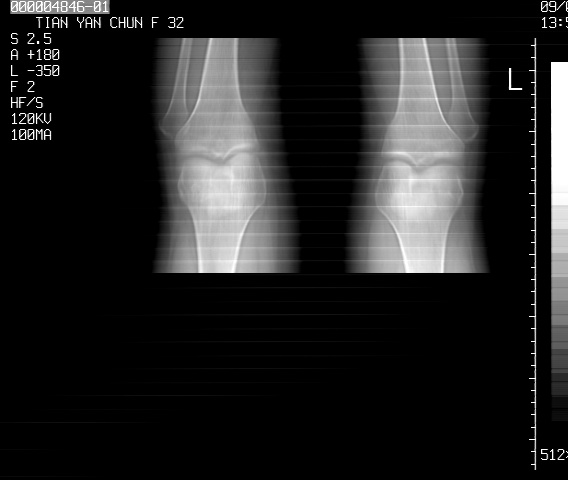

标题: CT18487:请会诊,女32岁,左膝疼痛数日 [打印本页]

标题: CT18487:请会诊,女32岁,左膝疼痛数日

定位片可见髁间棘骨质增生,支持膝关节退行性变。

关节面软骨有硬化环考虑退行性变

定位片可见髁间棘骨质增生,支持膝关节退行性变。建议mri 检查